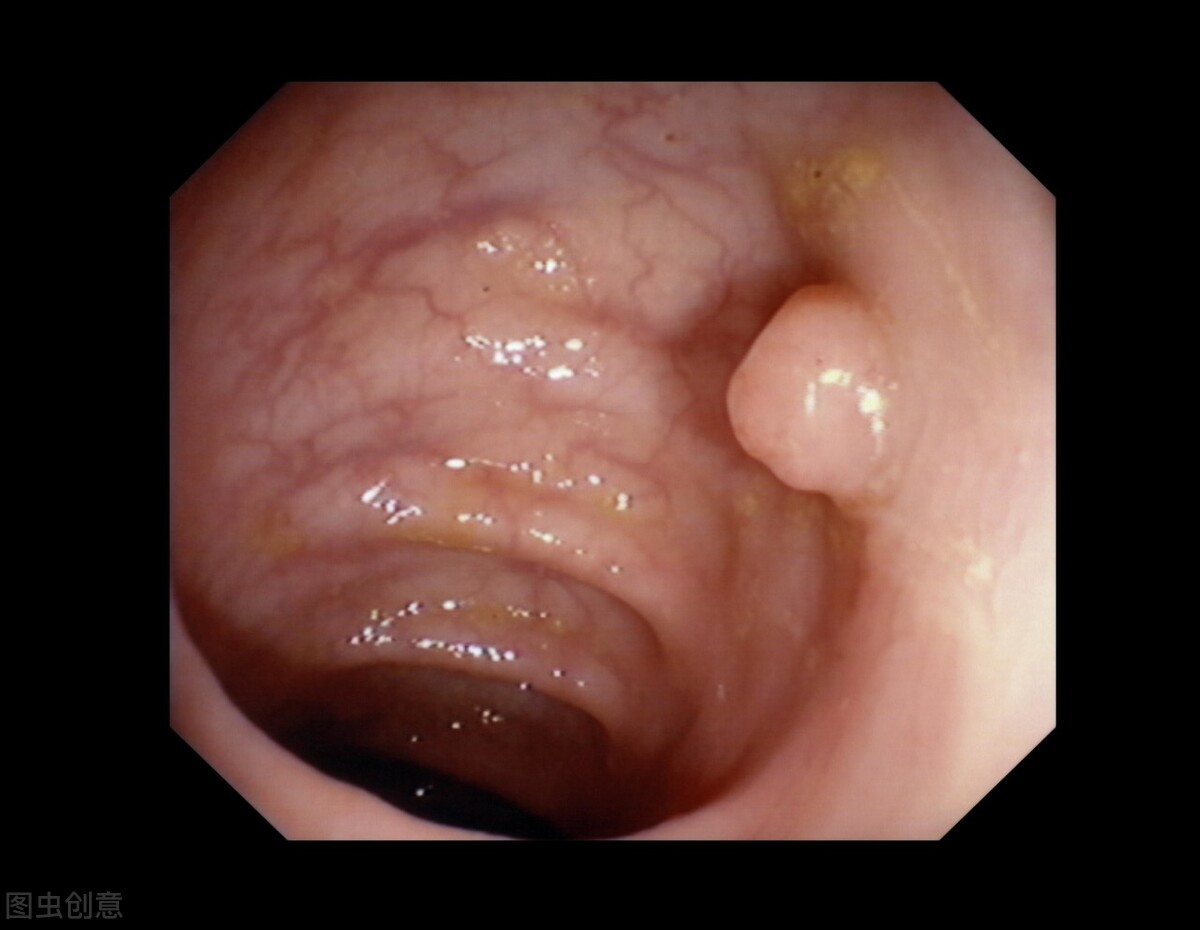

子宫颈息肉